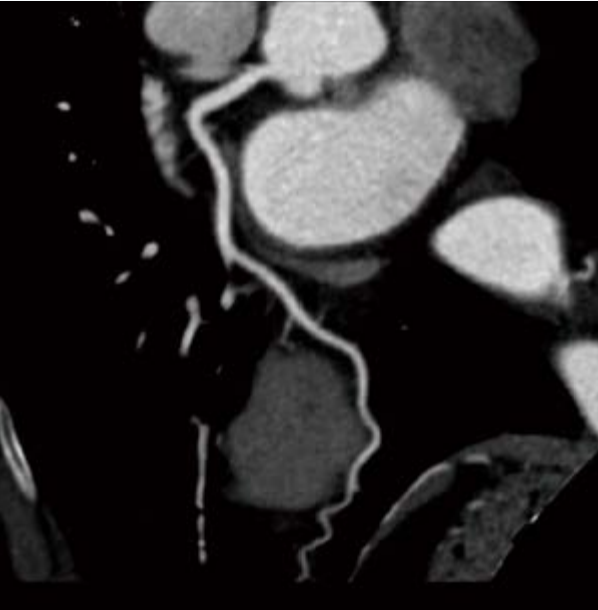

SinoVision Insitum 64s - это 64 срезовый КТ с большой апертурой гентри 75см. Один из самых доступных кардиологических компьютерных томографов. SinoVision Insitum 64 - это 64 срезовый КТ с большой апертурой гентри 76см. Уникальная интеллектуальная система управления стробированием SinoVision и алгоритм реваскуляризации коронарных артерий гарантируют мгновенное замораживание сердца и отображение структуры сердечно-сосудистой системы, стента, кальцификации, бляшек и другой информации в высоком разрешении.

- Интеллектуальная платформа коронарной визуализации мгновенно замораживает сердце и отображает информацию высокого разрешения о сердечно-сосудистых структурах, стентах, кальцификации и бляшках с помощью уникальной интеллектуальной системы управления и алгоритмов коронарной реваскуляризации SinoVision.

- Расширенный коронарный анализ

- Определяет степень стеноза и состав бляшки коронарной артерии, помогает при послеоперационном осмотре при шунтировании и стентировании

- Анализ стеноза коронарной артерии